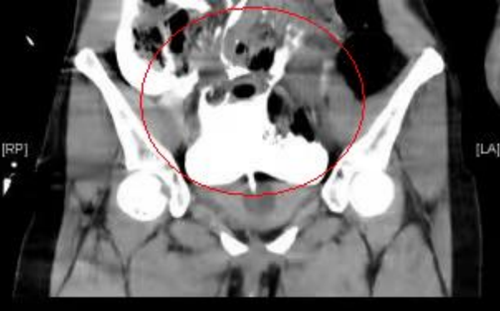

CT显示腹腔盆腔内大量积液(尿液),膀胱造影尿液混杂着造影剂,在盆腔、腹腔都显影出白色

根据张迪的描述,医生先为张迪行了妇科相关检查及腹部CT平扫检查,但是CT除了发现少量盆腔积液外未找到其它问题,考虑到患者腹痛在加重,急诊科医生紧急请泌尿外科前来会诊。泌尿外科医生仔细追问其病史,结合CT检查,考虑存在膀胱损伤可能,立即留置导尿管,见有少量淡红色血尿。最后经过膀胱造影CT检查,张迪确诊为腹膜内型膀胱破裂,腹腔内已有大量尿液,所以才引起腹膜炎刺激性腹痛等症状。